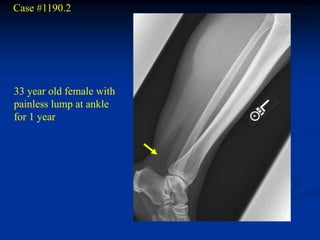

Case #270.1 Intramuscular lipoma Axial T-1 T-1 STIR 72 year female with painless mass in anterior thigh for years

• 24.

Coronal T-1 Sagittal T-1 Coronal STIR

• 25.

Case #270.2 Axial T-1 T-2 Gad 56 year male with painless soft mass in anterior thigh for 2 years

• 26.

Case #1190.2 33 yearold female with painless lump at ankle for 1 year

Sag T-1 PD Gad